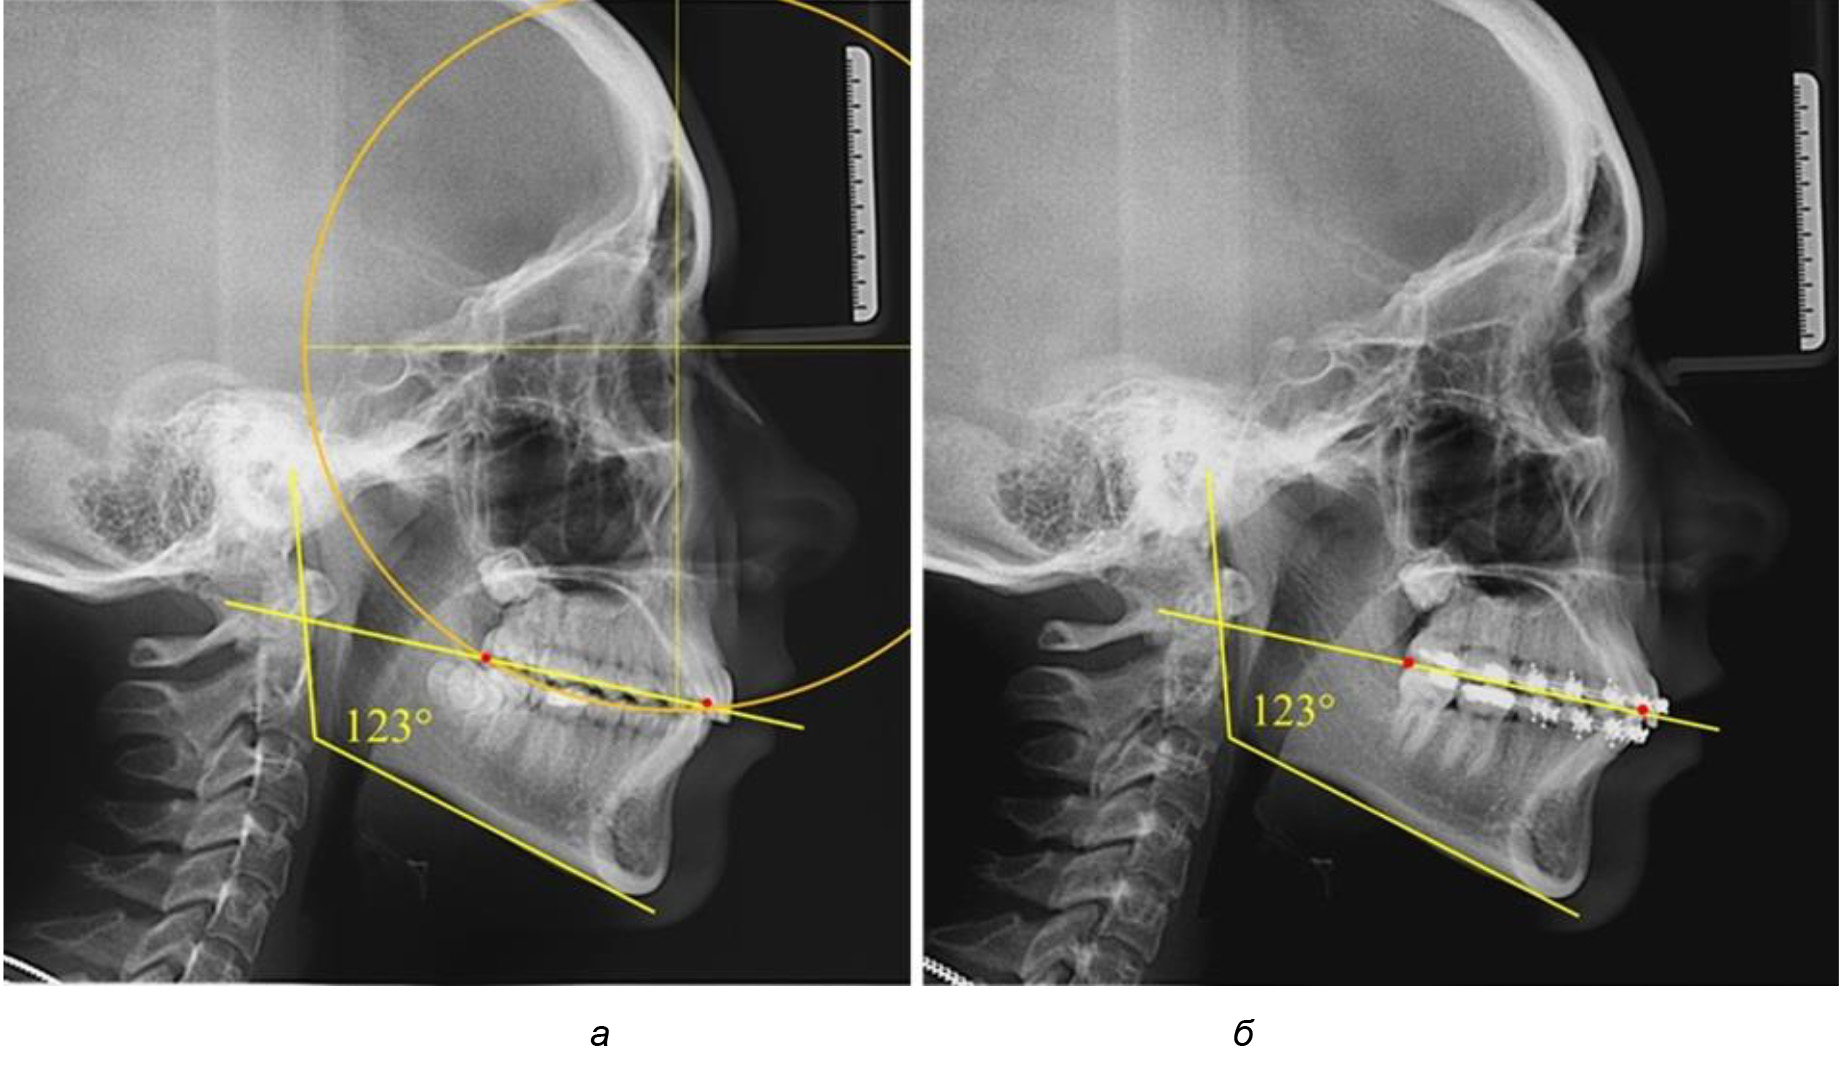

В 3-ю подгруппу вошли ТРГ и ОПТГ 14 человек 1-й группы, что составило (22,58 ± 5,31) % от общего количества людей 1-й группы. Величина угла нижней челюсти в среднем составила (114,85 ± 2,87)° и характеризовала горизонтальный тип нижней челюсти.

Глубина кривой Spee в среднем по 2-й подгруппе составил (2,94 ± 0,47) мм, что было меньше, чем в других подгруппах. Деление величины радиуса круга к длине окклюзионной линии составило 1,616 ± 0,02 (рис. 4).

Рис. 4. Особенности кривой Spee на ТРГ (а) и ОПТГ (б) у людей с горизонтальным типом лица